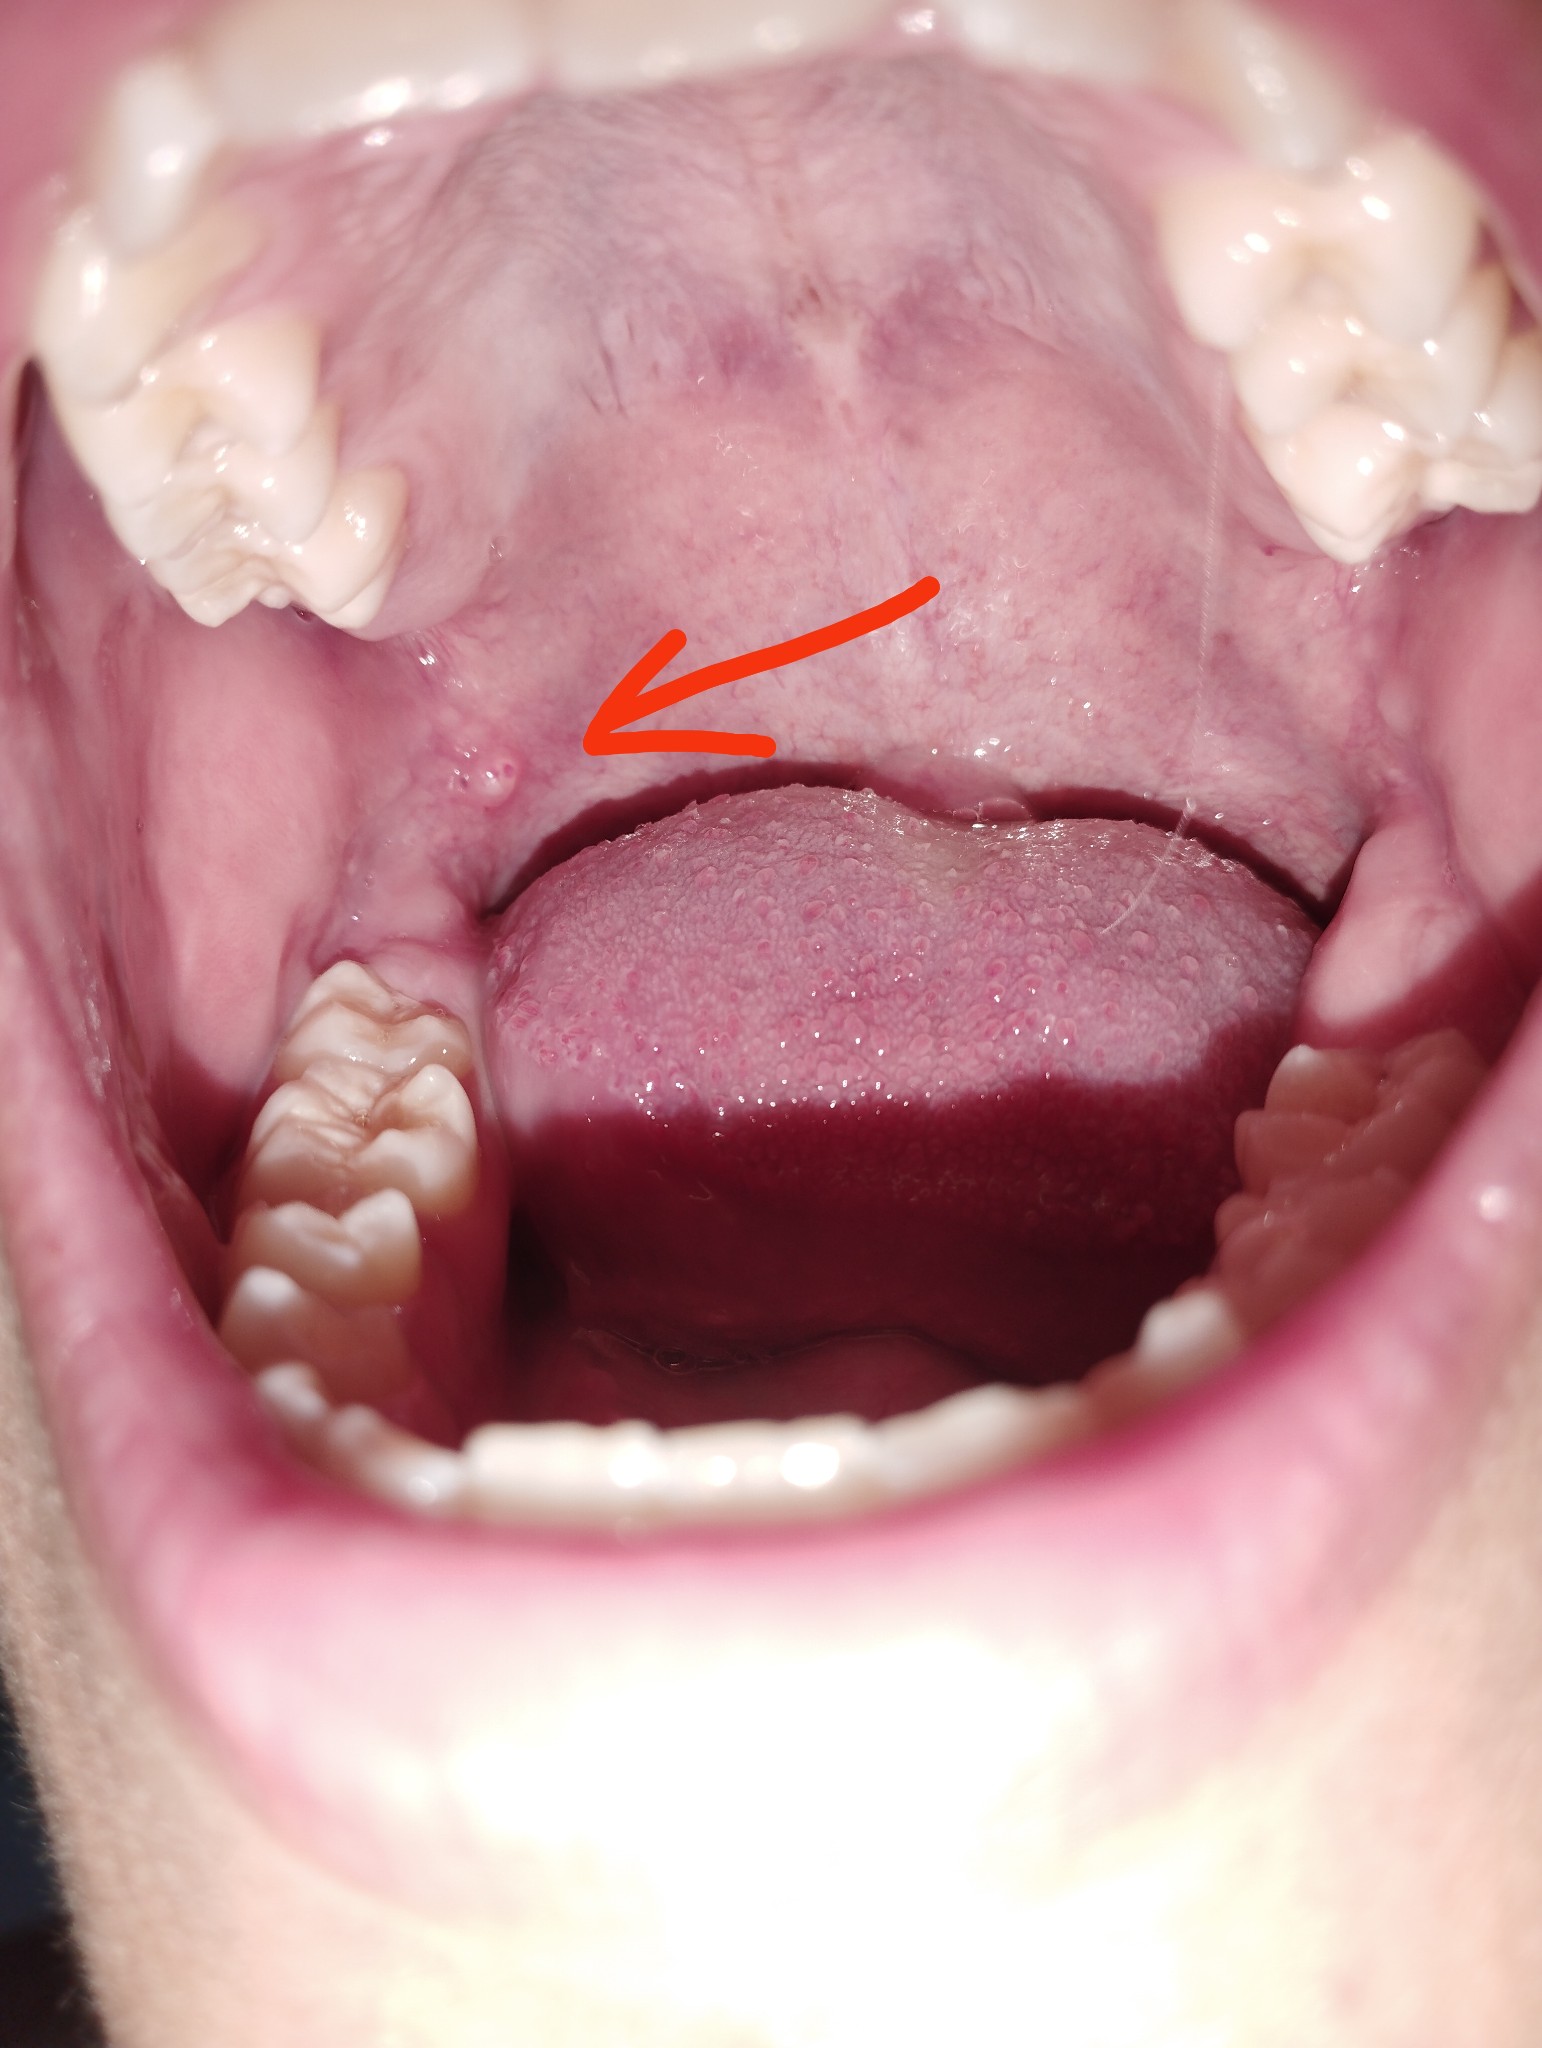

มันคืออะไรหรอครับมันเป็นเหมือนก้อนวงกลมใสๆนิ่มๆพอลิ้นไปโดนก็ไม่รู้สึกเจ็บ